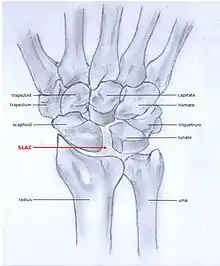

SLAC

Scapholunate advanced collapse (SLAC) is a predictable pattern of wrist osteoarthritis that results from untreated long-standing scapholunate instability, which in turn is secondary to a rupture of the scapholunate ligament.[5] The main type of such misalignment is dorsal intercalated segment instability (DISI) which is where the lunate angulates to the posterior side of the hand.[3][6]

SLAC and SNAC are two patterns of wrist osteoarthritis, following predictable patterns depending on the type of underlying injury. SLAC is caused by scapholunate ligament rupture, and SNAC is caused by a scaphoid fracture which does not heal and because of that will develop in a non-union fracture. SLAC is more common than SNAC; 55% of the patients with wrist osteoarthritis has a SLAC wrist.[4]